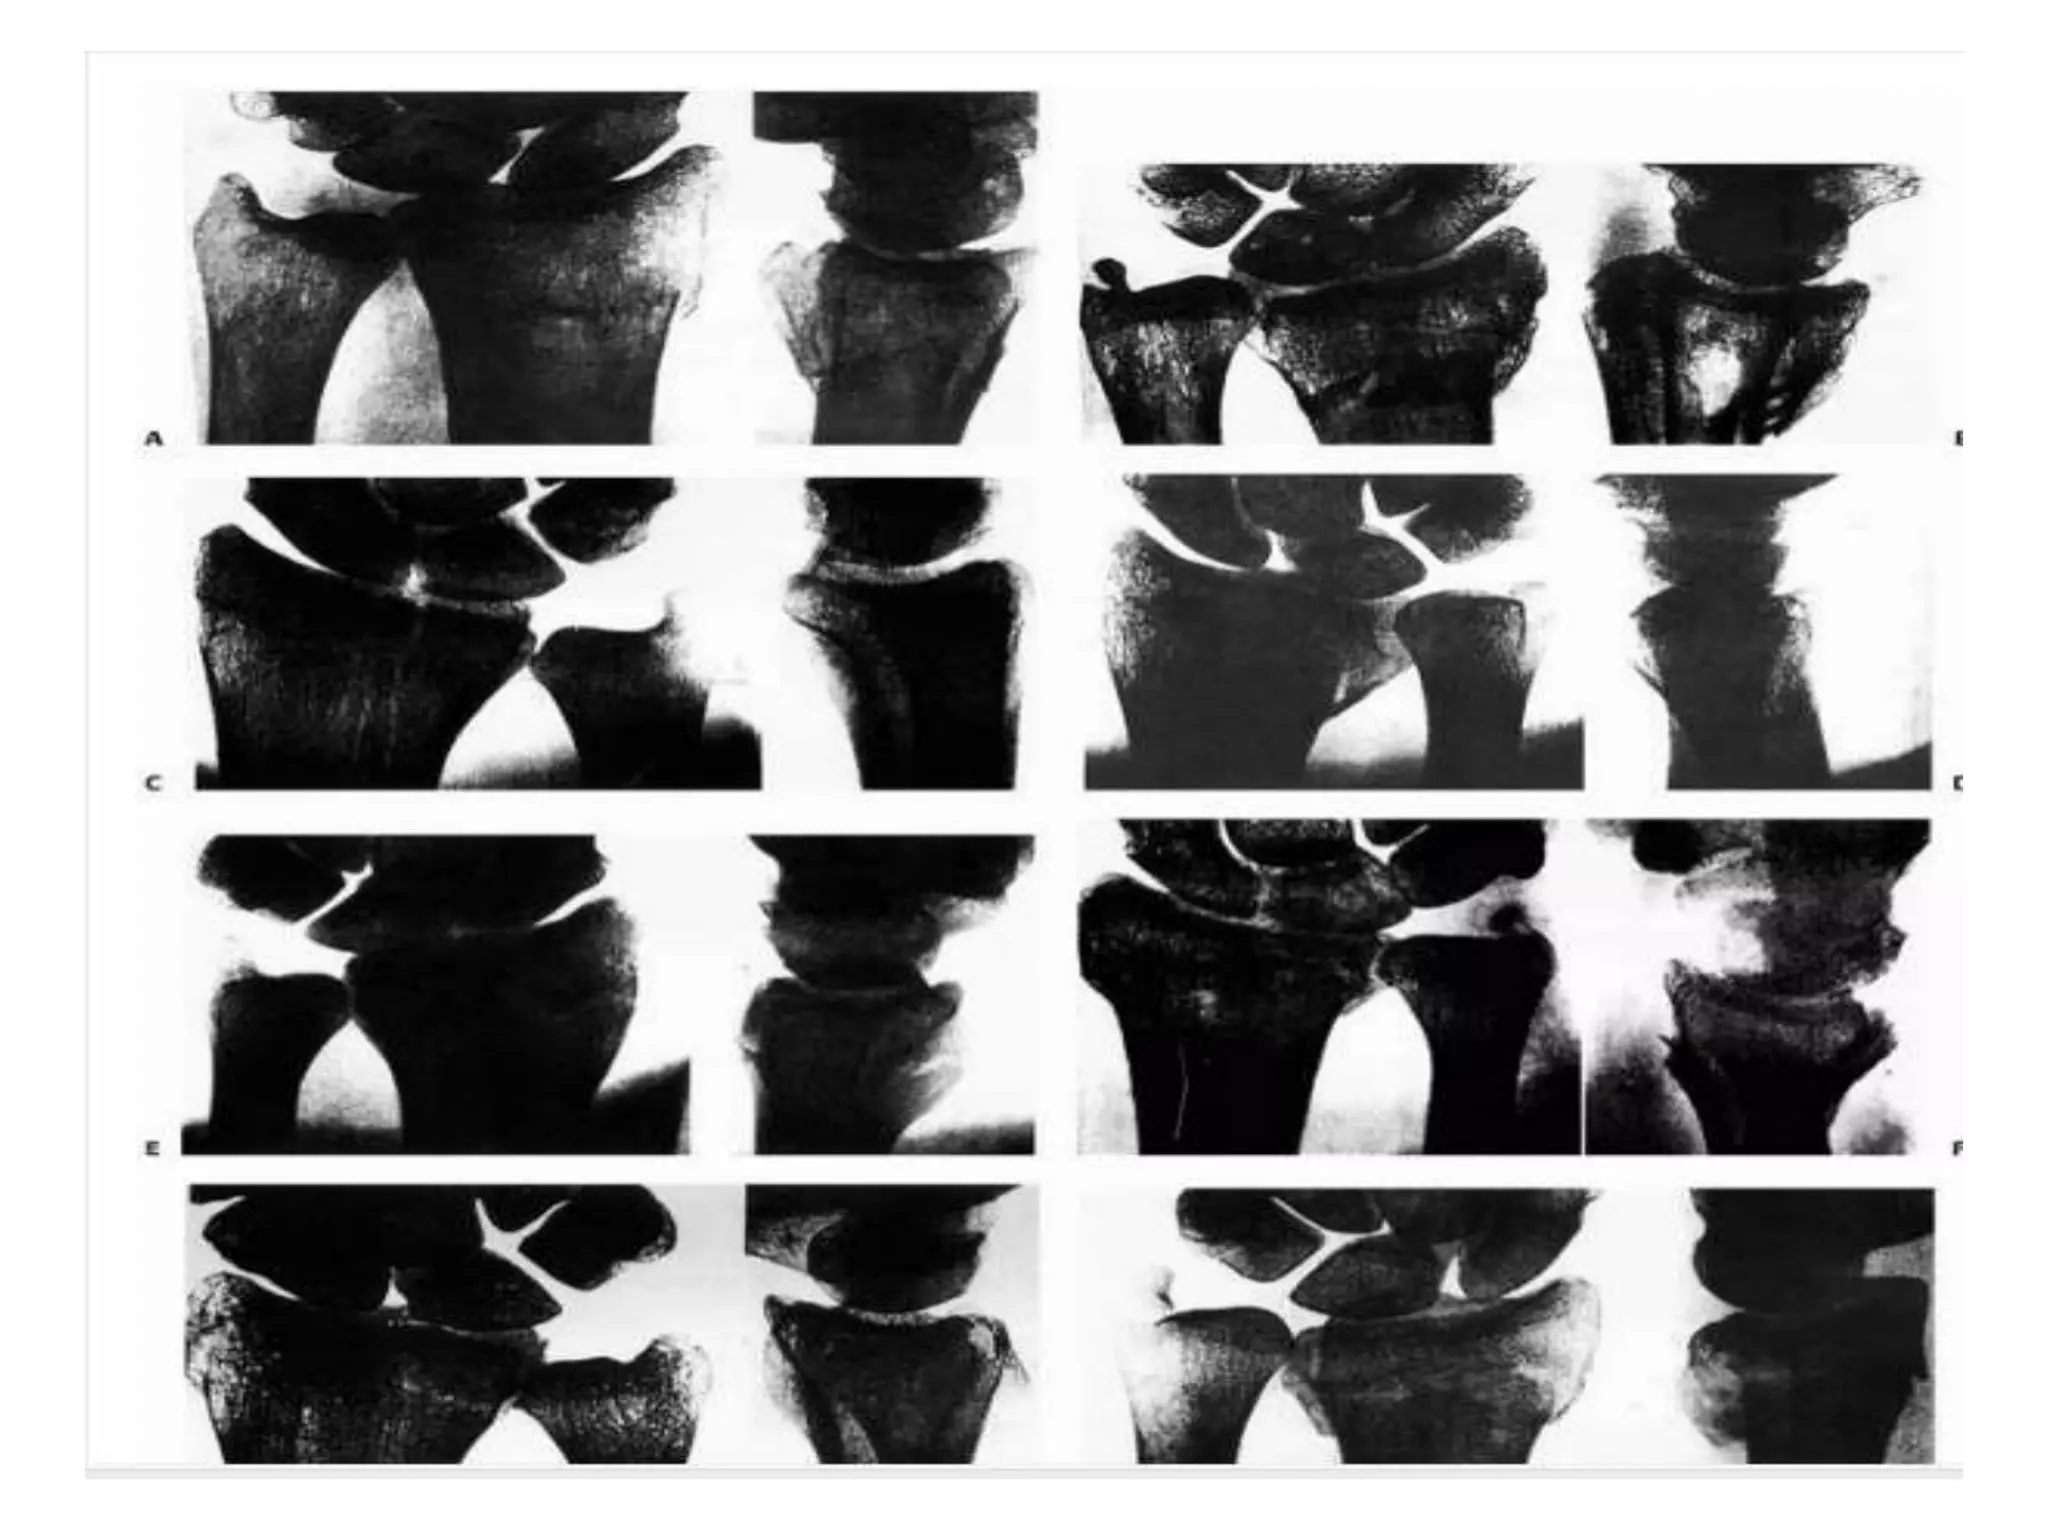

Frykman established a classification that incorporated

individual involvement of the radiocarpal and radioulnar

joints.

Type I: Extra-articular fracture

Type II: Extra-articular fracture with ulnar styloid fracture

Type III: Radiocarpal articular involvement

Type IV: Radiocarpal involvement with ulnar styloid fracture

Type V: Radioulnar involvement

Type VI: Radioulnar involvement with ulnar styloid fracture

Type VII: Radioulnar and radiocarpal involvement

Type VIII: Radioulnar and radiocarpal involvement with ulnar

styloid fracture

Frykman classification considers involvement of radiocarpal

& RU joint,

in addition to presnce or absence of frx of ulnar styloid

process;

classification does not include extent or direction of initial

displacement, dorsal comminution, or shortening of the

distal fragment;

hence, it is less useful in evaluating outcome of treatment;

such as Colles (dorsal angulation) or Smith (volar

angulation) fractures.